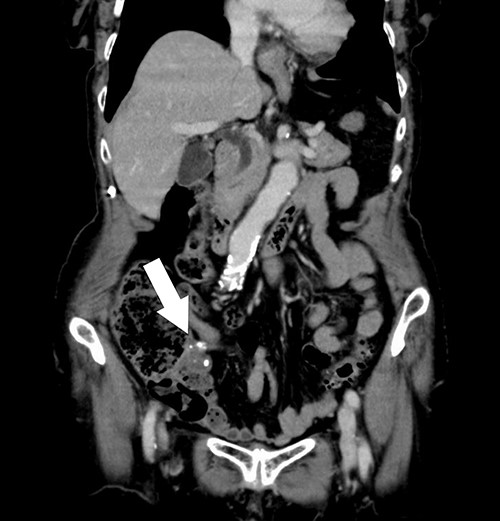

A 74-year-old female with hypertension, hyperlipidemia and hyperuricemia had a colonoscopy as a screening examination. The colonoscopy revealed an extrinsic compression with ulceration located at the cecum (Fig. 1). A multidetector computed tomography (CT) identified a low-attenuation distorted cystic lesion with focal calcification in the anatomic region of the right iliac fossa, measuring 6.1 × 5.0 × 3.7 cm (Fig. 2). Findings from the routine laboratory examinations were unremarkable, and all tumor markers were within normal range. The patient was scheduled for ileocecal resection with lymph node dissection due to the possibility of malignancy, such as appendiceal mucinous adenocarcinoma, because of the large and distorted tumor. Contrast-enhanced CT was conducted for further assessment of the findings, and we found that the cystic lesion was dramatically shrinking. It seemed improbable that rupture of the tumor had happened since no findings implied the spread of mucinous components, such as ascites or mucinous peritoneal nodules on CT. It was considered that the mucinous content was spontaneously drained from the root of the appendix to the cecum. However, the enhanced and distorted lesion with focal calcification, suggesting malignancy, had remained in concordance with the base of appendix (2.7 × 2.1 × 1.9 cm) (Fig. 3). Therefore, ileocecal resection was performed as planned, and laparoscopic procedure was selected due to the unlikelihood of the tumor rupturing. The base of appendix was distended and there were no obvious peritoneal anomalies upon visualization of the abdomen (Fig. 4). The specimen was handled with care and there was no spillage of cystic contents. The post-operative course was uneventful, and the patient was discharged on post-operative day 8.

Contrast-enhanced CT showing the enhanced and distorted lesion with focal calcification (arrow).